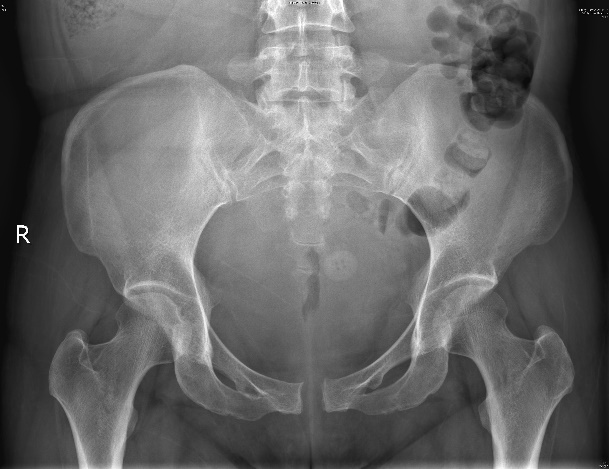

萍萍(化名)是一个二胎妈妈,前不久顺产生下一个4.55公斤的男婴。然而,分娩的喜悦并未持续太久,产后的第一天,萍萍发现自己不能翻身,无法下床,走路也走不了,连侧身喂奶都疼,严重影响到日常生活。我院妇产儿保医学中心辛长征主任医师立即为她做骨盆平片,发现耻骨联合分离达16mm。

耻骨联合分离16mm

然而,当胎儿体重过大或分娩过程中受力过大,间隙超过生理宽度,导致耻骨区域疼痛严重,影响走路,甚至伴有腰背和下肢酸痛,可能发生了耻骨联合分离。围产期耻骨联合分离是产科临床较常见的一种并发症,是产前或产后发现耻骨联合间距(X光正位片上的耻骨联合之间的最小距离)大于10mm,同时合并局部肿胀、疼痛、髋关节活动障碍等临床表现。